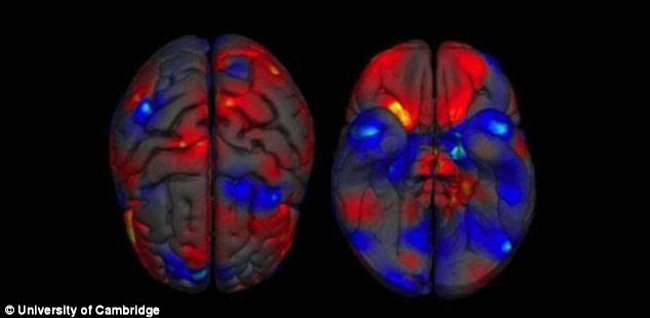

Research shows that: " Men and women 's brains are not much different ." Researchers have found structural differences between the brains of men and women, but they cannot identify individual sex based on the MRI of the brain as shown below.

So in the most recent study, behavioral neurologists led by Daphna Joel at Tel Aviv University in Israel instructed team members to try to improve as much as possible. By using available MRI images of the human brain, they measure the amount of gray matter (many nerve nodes linked together, the central point of nerve cells) and white matter (a group of fibers neurons transmit signals to the nervous system) among more than 1400 human brains. They also studied data from tensor diffusive images showing how to stretch white matter in the brain and connect with other areas.

The team has found a number of different structures between men and women. For example: Hippocampus (hippocampus) left is the area inside the brain related to memory and men are often larger than women. However, in each area there is quite a lot of overlap, for example, some women have Hippocampus bigger or more like men, while some of Hippocampus of men are smaller than The average magnitude of women.

To accommodate this overlap, researchers created a continuous connection of " feminine" to " masculine " for the entire brain. The limited area of men contains more typical features of men and the limited areas of women have more structures common in women. After that, this research group focused on each specific area to find continuous gender differences.

The research team published it directly on the Proceedings of the National Academy of Sciences: " Most brains are a mosaic of male and female structures ." It depends on whether the researchers can see the gray matter, white matter or tensor diffuse image data. Approximately 23% and 53% of the brain contains a mixture of regions located in the spectral end area in both men and women. Very few - only about 0% to 8% - the brain contains the entire structure of men and women. "Joel said:" There is no specific characteristic of the male brain and the brain. female ".